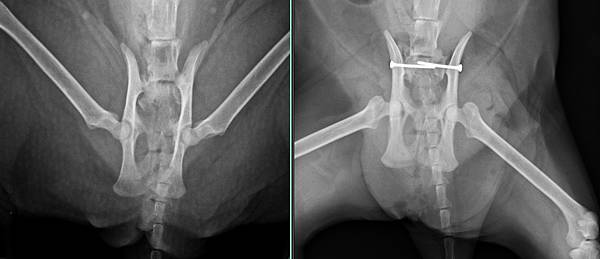

骨盆脫臼/雙側腸薦關節脫臼

於是安排手術修復